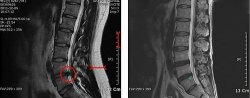

박원순 서울시장 아들 측 엄상익 변호사는 강용석 의원이 제기한 박 시장 아들의 병역 관련 MRI(자기공명영상진단) 사진 의혹에 대해 "필요하다면 서울대 병원에서 다시 검사를 받아 이중 삼중으로 크로스 체크할 수도 있다"고 밝혔다.